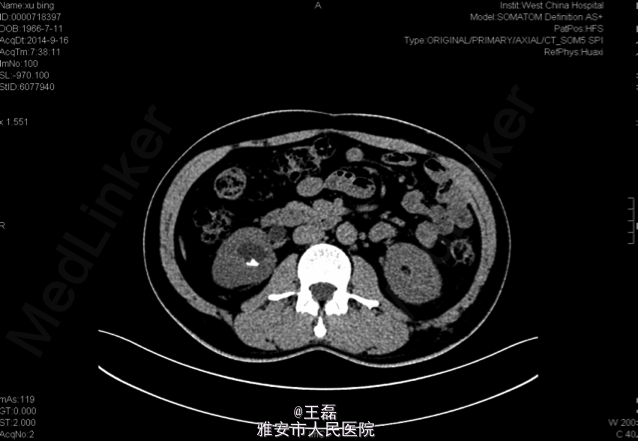

患者49岁男性,因右腰部隐痛不适入院

术前KUB:右肾结石:1.0*0.9cm

诊断为右肾下盏结石; 手术:右侧输尿管软镜钬激光碎石取石术